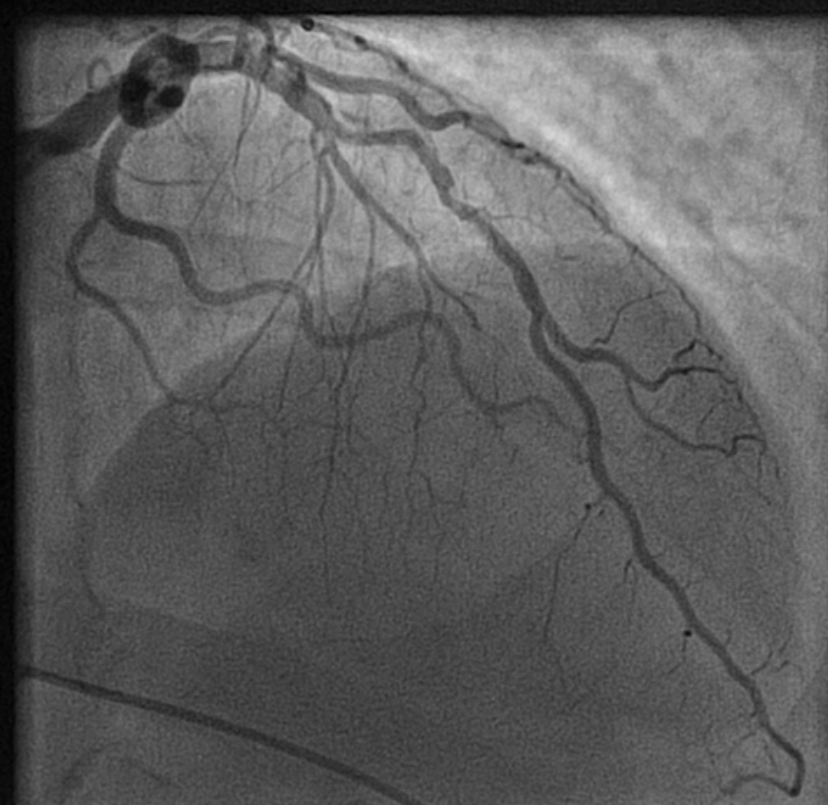

How to tackle this stress positive Intermediate LAD lesion. Functional capacity good. Non-diabetic, mildly elevated lipids. Now, continuing medical management with intensive lipid control is the best possible management. (We have evidence for medical management being good even in significant 90% lesion) Above is a case report from https://www.acc.org/education-and-meetings/patient-case-quizzes/medical-therapy-for-cad

Reassurance is a revascularization equivalent

Sharing a similar experience with one of my patients in his early fifties. After getting a fairly convincing consultation, he accepted medical management. However, guided by both NI & AI, he sought a second opinion to confirm whether my assurance was indeed correct. He underwent FFR and OCT, and both he and his plaque became vulnerable. The FFR was normal. He was too intelligent to ask about the FFR – Stress test discordance, for which his cardiologist had no answer. Still, they did not advise a PCI and the decision was left to him, respecting the current patient-oriented guidelines.

The patient went home empowered but spent sleepless nights, fearing about potential fissures, in the life sustaining fibrous cap.He believed that he was at the mercy of a 75-micron thin cap covering his plaque. In one of the anxious days,in the following week , he got admitted himself in a posh downtown cardiac center. A as per the guidelines, the patient chose his own pathway for a PCI. Cardiologists obliged piously to his wishes. Now, he feels better. He says he is happy to undergo a self prescribed stent.